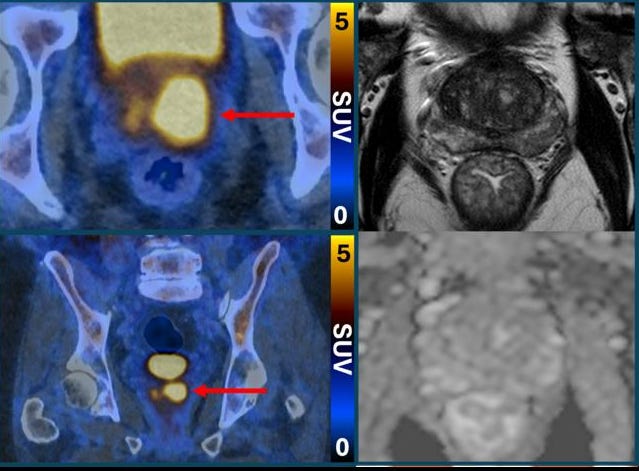

🔬 Un examen qui rend les cellules cancéreuses de la prostate fluorescentes pourrait réduire le besoin de biopsies !

Une étude récente, présentée lors du congrès de l’Association européenne d’urologie (EAU26), montre qu’un examen d’imagerie, la TEP/TDM au PSMA, pourrait diminuer de moitié le nombre de biopsies chez les personnes suspectées d’un cancer de la prostate après une IRM non concluante. Cette technique utilise une molécule qui rend les cellules cancéreuses fluorescentes, facilitant leur détection. L’essai PRIMARY2, mené en Australie, a suivi 660 patients et démontre que cette approche permet d’identifier les cancers agressifs tout en évitant les biopsies inutiles pour les cas à faible risque.

😀 Pourquoi c’est bien ?

Cette innovation offre une alternative moins invasive et plus précise pour les patients, réduisant l’anxiété et les effets secondaires liés aux biopsies. Elle permet aussi de limiter le surdiagnostic, en ciblant uniquement les cancers nécessitant un traitement. Selon les experts, cette méthode pourrait transformer la prise en charge du cancer de la prostate, en optimisant les soins et en améliorant la qualité de vie des patients.